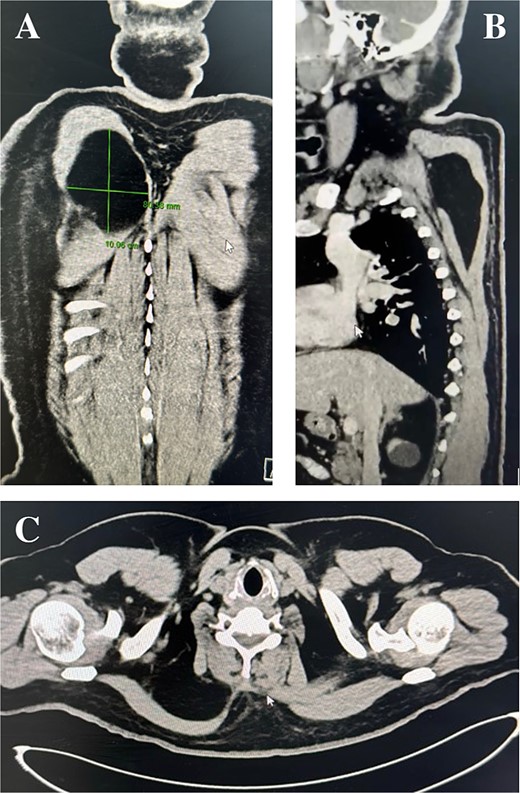

Physical examination identified a well-circumscribed mass measuring 15 cm × 20 cm in the right scapular region. A computed tomography (CT) scan showed a low-attenuation intramuscular mass without calcification (Fig. 1A-C). A magnetic resonant imaging (MRI) scan was recommended as the primary investigation, but the patient refused. Surgical excision was performed with the patient in the prone position (Fig. 2A). A 15 cm incision was made between the spinal process and the scapula’s medial border (Fig. 2B). Subcutaneous flaps were raised, revealing the palpable mass beneath the trapezius and rhomboid muscles. The mass, appearing benign, was removed and sent for histopathological analysis (Fig. 2C and D). The muscle fascia was repaired, and the incision was closed in layers over a surgical drain. The procedure was uneventful, and the patient was transferred back to the ward.

Computed tomography scan: Coronal, sagittal, and axial planes of the lipoma.